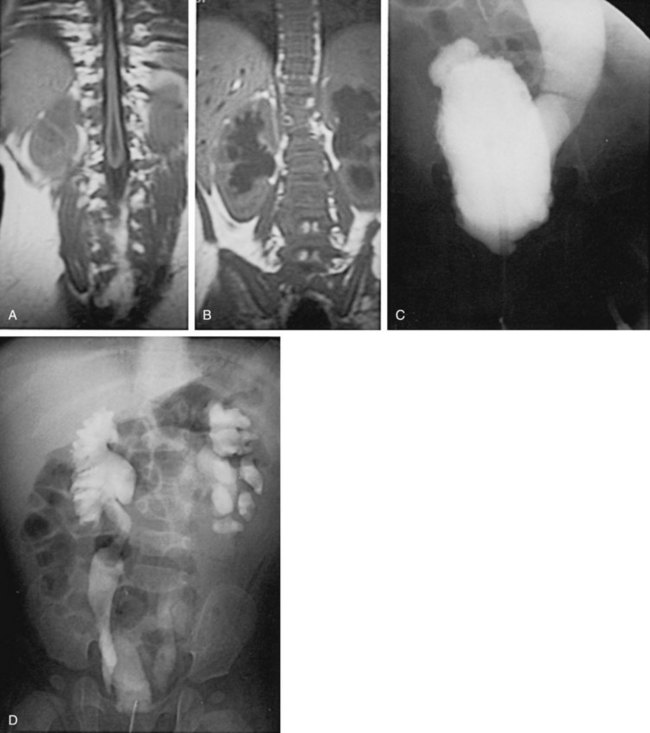

The neurologic lesion in myelodysplasia is a dynamic disease process in which changes take place throughout childhood (Epstein, 1982; Reigel, 1983; Venes and Stevens, 1983; Oi et al, 1990), especially in early infancy (Spindel et al, 1987) and later at puberty (Begger et al, 1986), when the linear growth rate accelerates again. When a change is noted on neurologic, orthopedic, or urodynamic assessment, radiologic investigation of the CNS often reveals (1) tethering of the spinal cord (Fig. 128–6), (2) a syringomyelia, a dilation and fluid collection within the spinal cord, (3) increased intracranial pressure due to a shunt malfunction, or (4) partial herniation of the brainstem and cerebellum. Children with completely intact or only partially denervated sacral cord function are particularly vulnerable to progressive changes. Magnetic resonance imaging (MRI) is the test of choice because it reveals anatomic details of the spinal column and CNS (Just et al, 1990). However, it is not a functional study and when used alone it cannot provide exact information about a changing neurologic lesion.

Figure 128–6 MR image in a 9-year-old girl who developed a tethered cord after myelomeningocele repair reveals the conus opposite the L3–4 vertebrae (arrow).